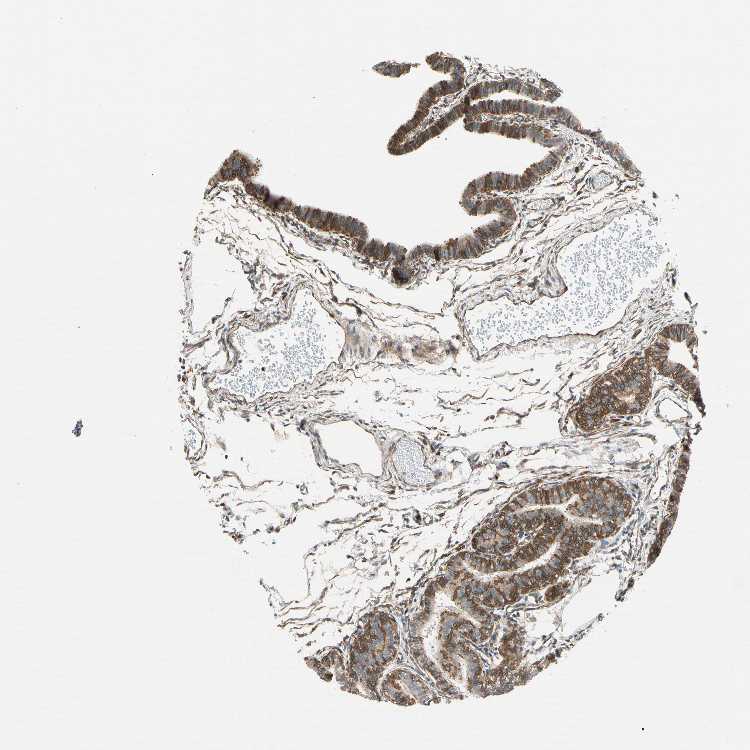

TISSUE PRIMARY DATA FALLOPIAN TUBE Show tissue menu

FALLOPIAN TUBE - Antibody stainingi

Antibody staining in the annotated cell types in the current human tissue is reported as not detected, low, medium, or high, based on conventional immunohistochemistry profiling in selected tissues. This score is based on the combination of the staining intensity and fraction of stained cells.

Each image is clickable and will lead to virtual microscopy that enables deeper exploration of all samples and also displays staining intensity scores, fraction scores and subcellular localization as well as patient and tissue information for each sample.

Antibody HPA009087Antibody HPA013210

Glandular cells HighMedium